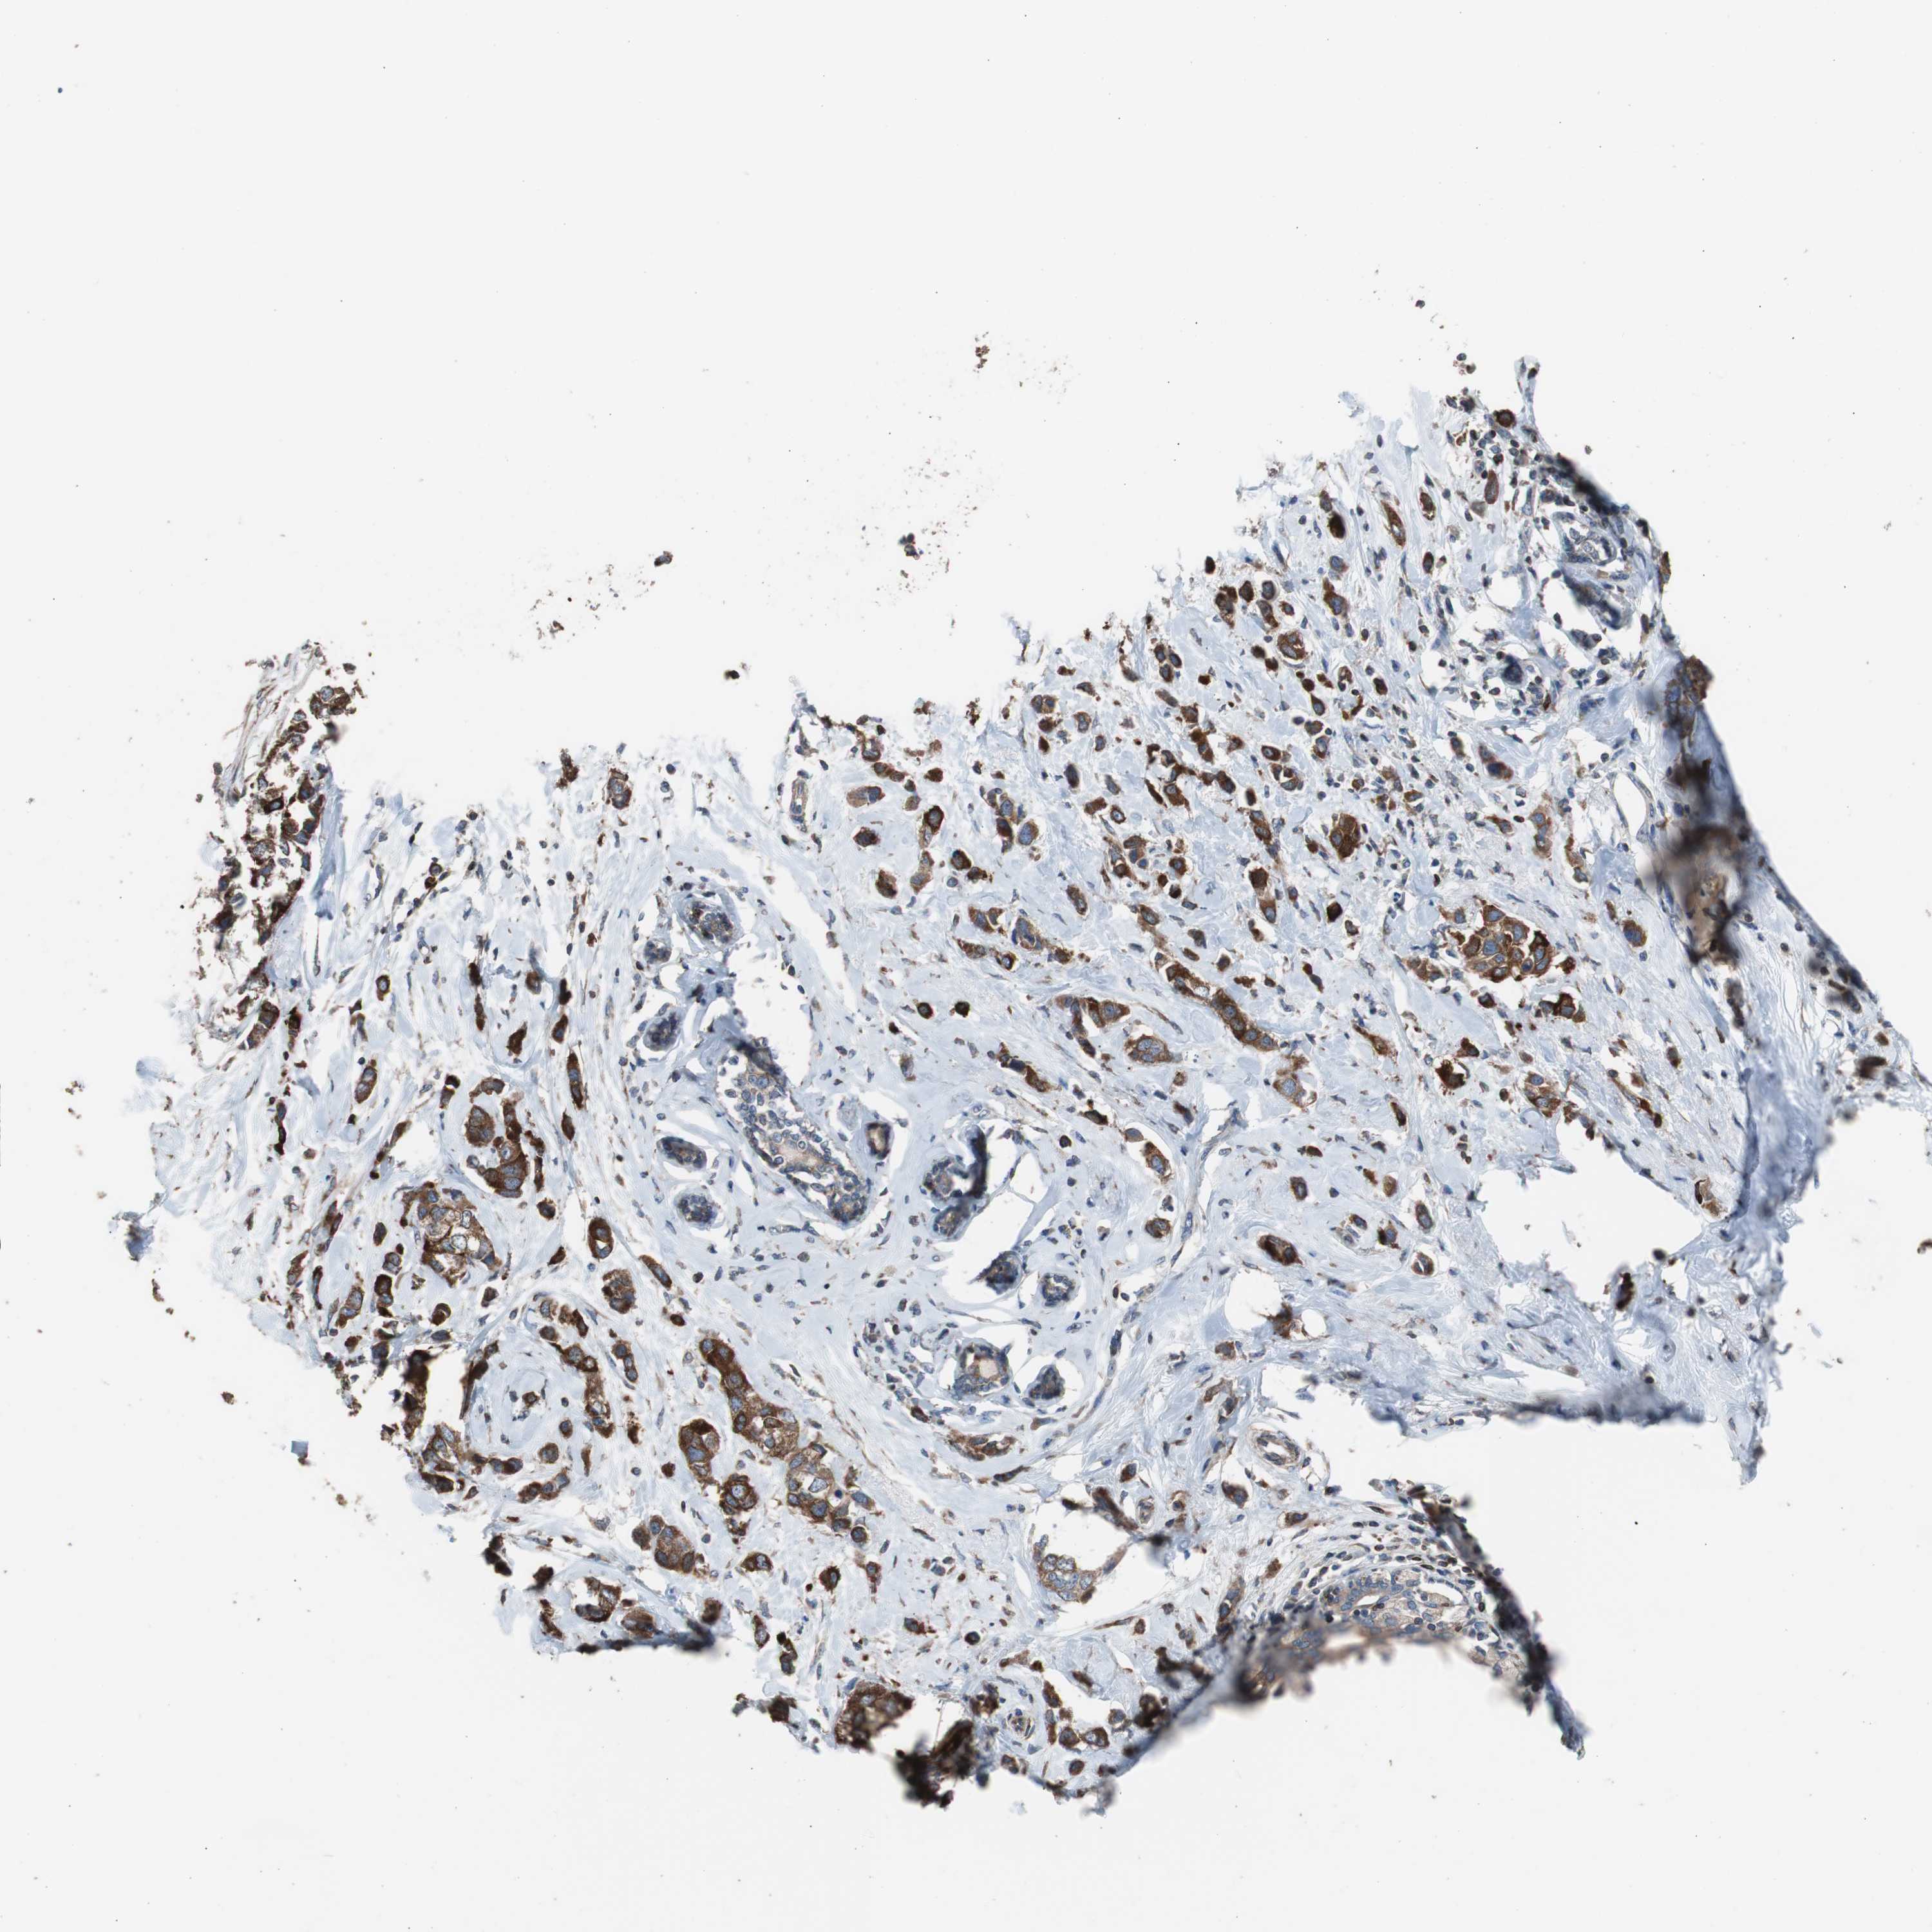

BRCA TCGA BRCA VALIDATION PROTEIN EXPRESSION

ANTIBODIES

AND

VALIDATION